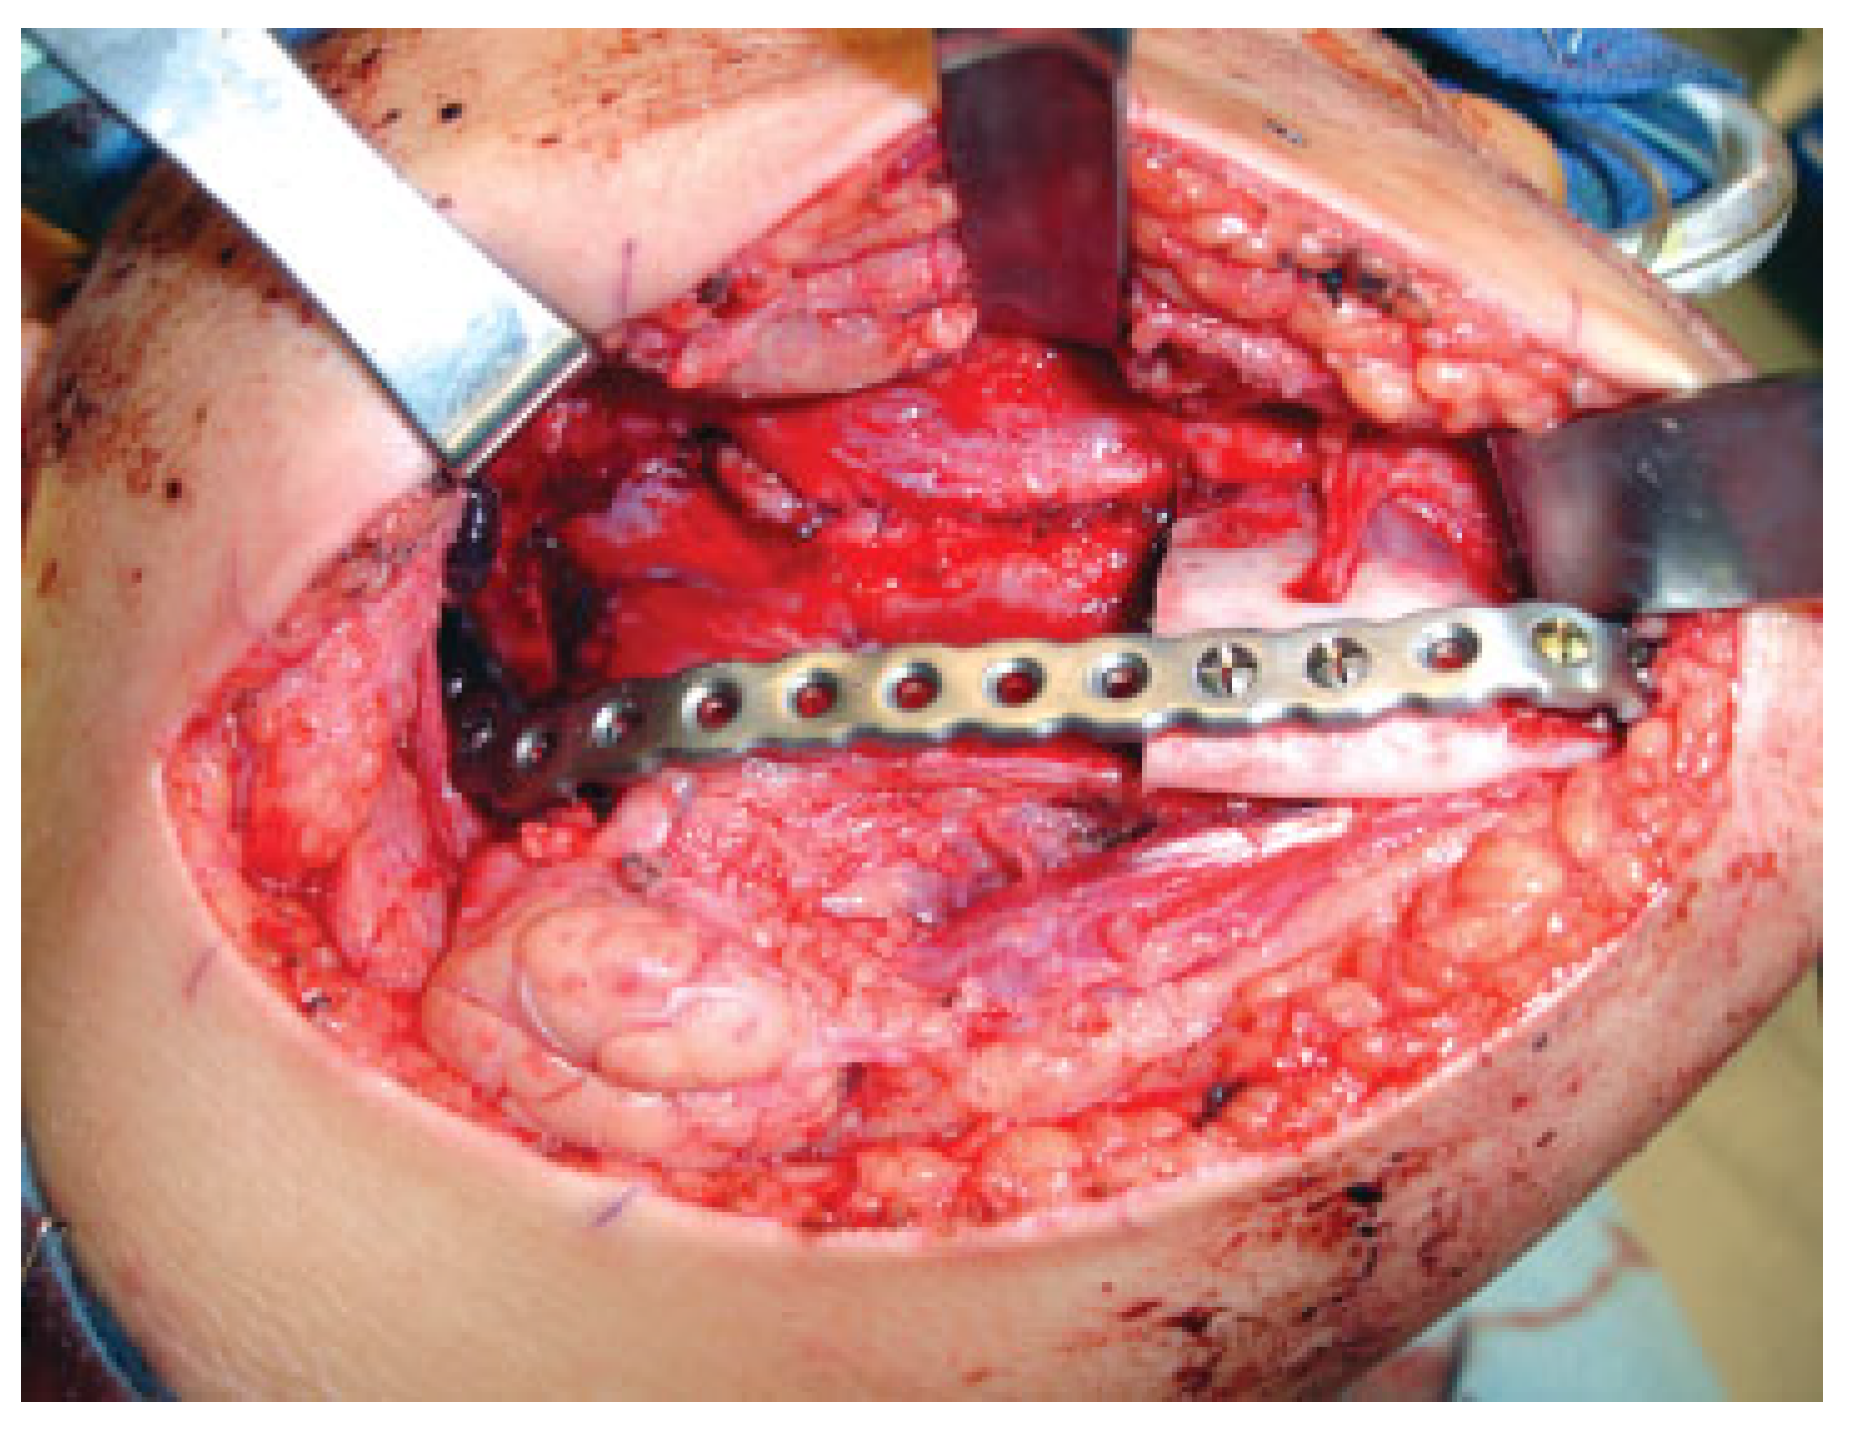

The fourth case was a 9-year-old white male referred to our service with a biopsy-proven ameloblastoma of the right mandible. Panoramic radiographic examination showed a unilocular radiolucent lesion extending from the right first mandibular molar up into the ascending ramus (Figure 4). A high-resolution CT scan was followed by the construction of a three-dimensional model (Figure 5). The resection with 1-cm margins was planned over the model extending vertically from the right sigmoid notch to the gonial angle and anteriorly through to the ipsilateral first premolar. Because of the marked lateral expansile nature of the lesion, the model and the specimen (prior to resection) were altered at the area of the inferior border to facilitate hardware adaptation (Figure 6). A prebent reconstruction plate was obtained and sterilized preoperatively. The resection was performed via a combined transoral and transcutaneous approach. Screw holes were drilled using the prebent plate as a template prior to completing the osteotomies. This was done to ensure correct position of the segments. After the resection, the plate was repositioned without modification utilizing the previous predrilled holes (Figure 7). The occlusion was assessed intraoperatively and was found to be unchanged from preoperatively. The total surgical time was 3 hours and 34 minutes.

One of the difficulties we encountered was the bending of the plate over a deformed model due to an expansile lesion. We solved this issue by modifying the model using the opposite site as reference (Figure 6). Coward et al. [8] described a technique to create a mirror image wax model for reconstruction of an ear using the contralateral unaffected side. Using the same principle, Hannen [9] reported two cases in which, with the help of software, the corresponding unaffected area from the contralateral side was digitally separated, mirrored, and fitted into the resection defect, obtaining a symmetric model used as a template for custom-bent plates. Another common complication is placement of the plate before performing the osteotomies. This was done on cases 4 and 5 with the objective of recording the position of the segments prior to resection. Modifying the mandible at expense of the tumor violates the oncological surgical principles and is not viable on the deformed morbid anatomy secondary to malignancy. An external pin fixation device could be placed to accomplish this goal when the screw holes cannot be drilled before the resection.

Figure 6. The altered model and specimen to facilitate adaptation of the plate prior to resection. This step will ensure correct contour and position of the segments after resection. Case 4.